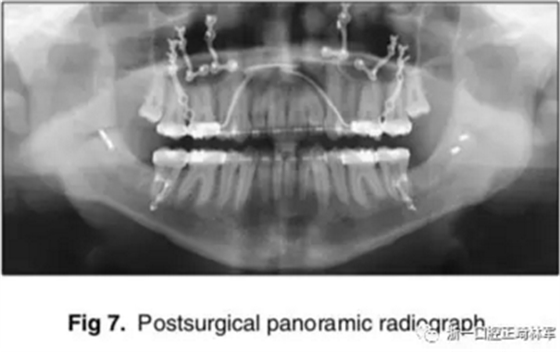

手術(shù)先采取下頜骨雙側(cè)矢狀劈開截骨術(shù),使用中間合板確定下頜位置。當(dāng)下頜骨位置穩(wěn)定后,使用堅(jiān)固內(nèi)固定固定下頜骨,移去中間合板。隨后,上頜行LeFort I型截骨術(shù),按照Dolphin軟件的計(jì)算前移7mm;通過終末合板確定上頜骨的位置,再使用鈦釘進(jìn)行堅(jiān)固內(nèi)固定。拔除第三磨牙;同時,在顴突處植入微鈦板,使用骨皮質(zhì)螺釘固定。

術(shù)后,患者即刻獲得了I類側(cè)貌,II類尖牙關(guān)系。

影像學(xué):全景片示:牙根平行度可。頭顱側(cè)位片及疊加圖示:顯著的骨性、牙性改變;其中,最大的改變?yōu)樯舷骂M位置關(guān)系,改變了7mm;由此帶來的改變?yōu)锳NB角從-4°變?yōu)?°,Wits值由-10mm變?yōu)?1.5mm,上頜突度減?。ˋ-NPer,3mm),上下頜不調(diào)改善(Co-A-Co-Gn,41mm),從而使側(cè)貌更為平直;下頜磨牙遠(yuǎn)中移動,無伸長、傾斜,反映了下頜整體的遠(yuǎn)中移動;上下切牙傾角糾正(1:NA,7mm、25°; 1:NB,4.5mm、20°; IMPA,78°),從而改善了在基骨中的位置。